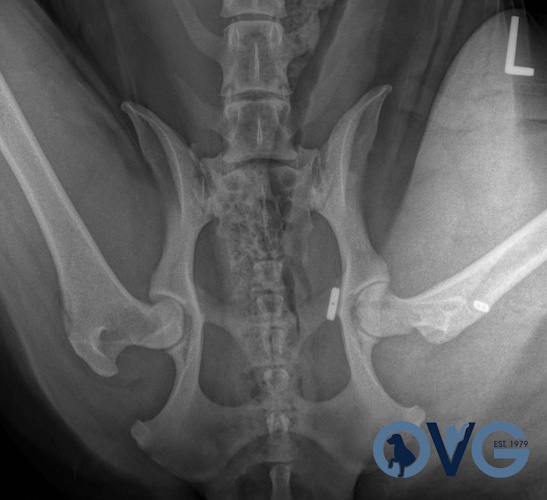

Coxofemoral Luxation (Hip Dislocation)

Hip Dislocation in canines

Treatment Option for Hip Dislocation

Post-op of a Hip Replacement